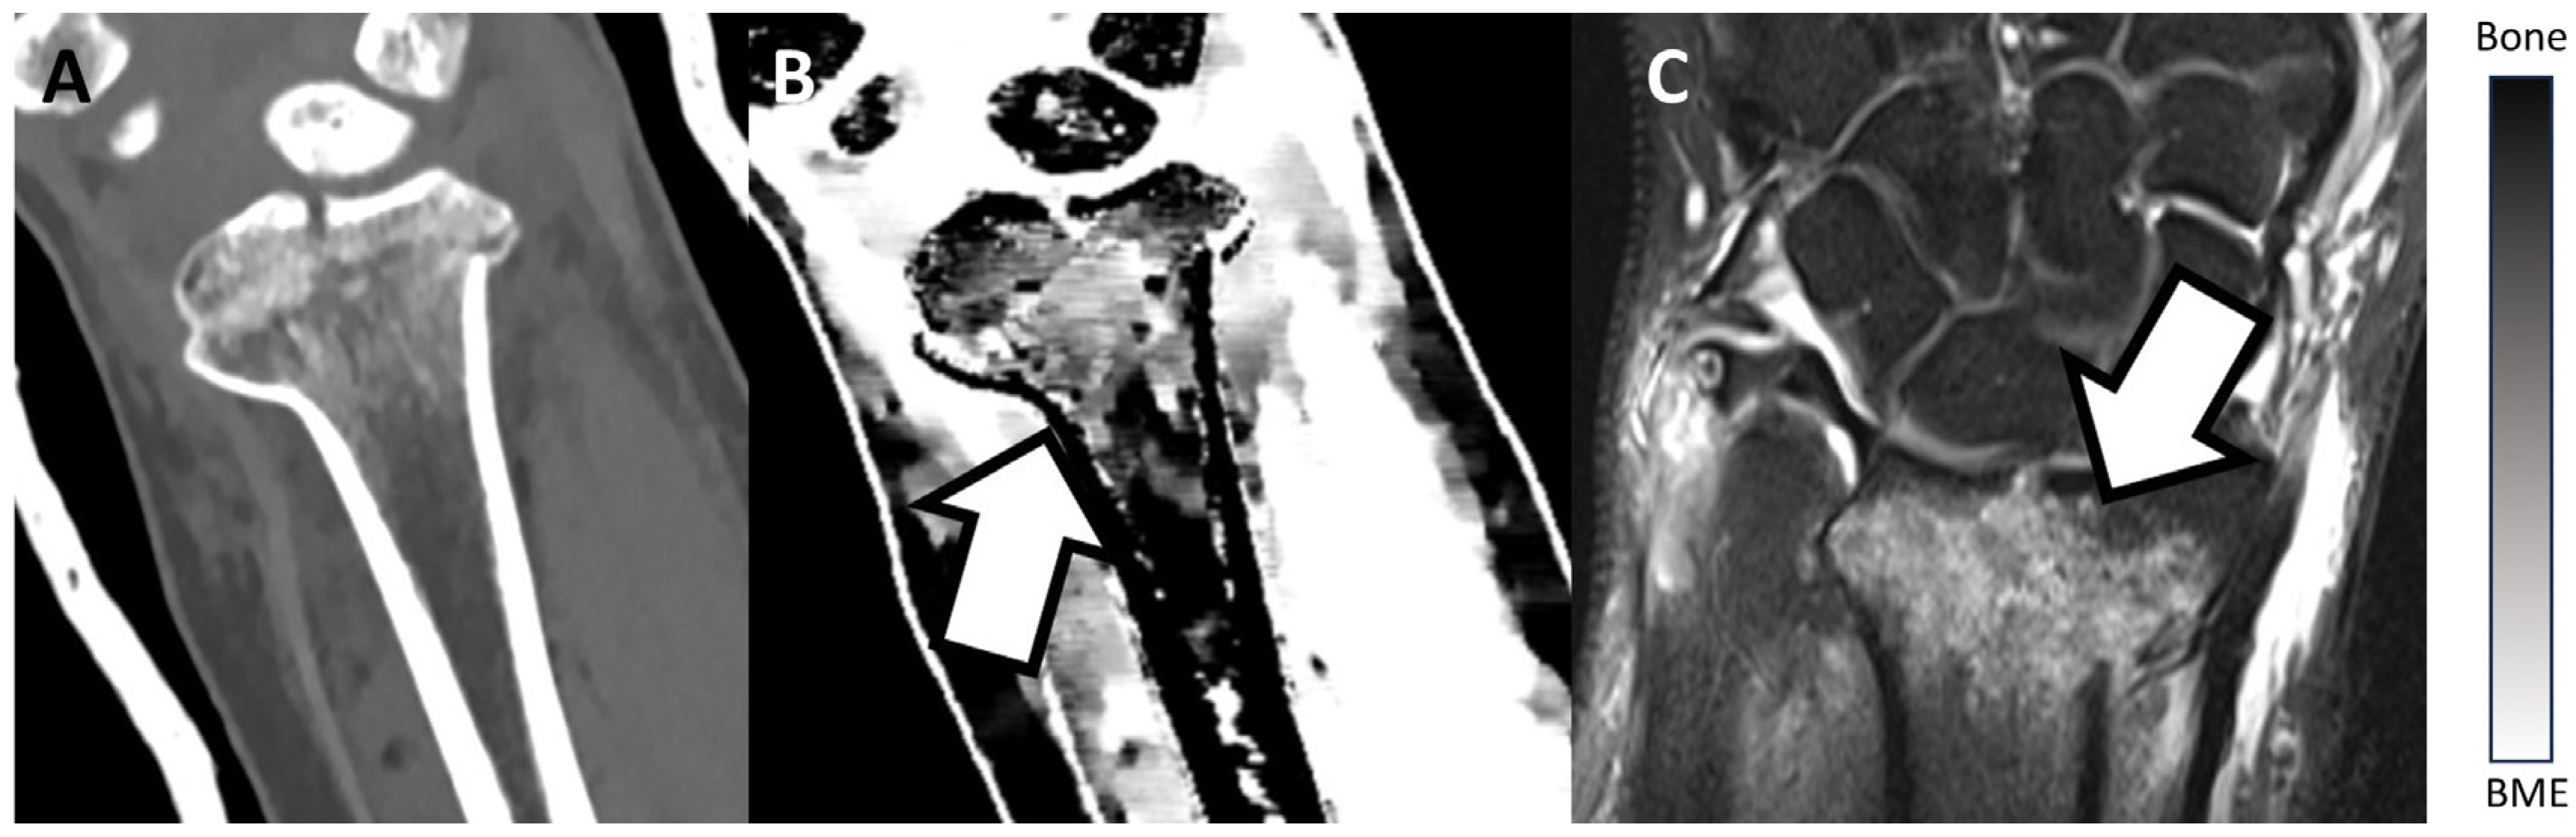

3.2. Examples